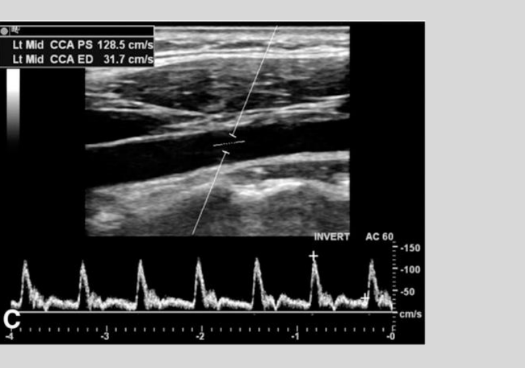

what is this waveform showing?

Cardiac Arrythmia

Bigeminy: irregular beat that

is followed by a normal beat